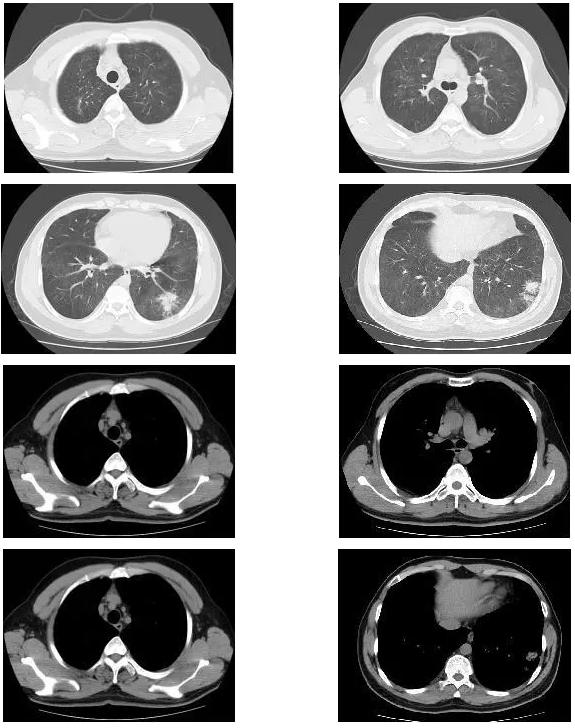

复查胸部CT(2018-1-29),对比原片如下图:

1、两肺野弥漫病变较前未见明显变化,两肺上叶陈旧病变同前

2、左肺下叶片状密度增高影较前范围增大,密度增高

3、纵膈内多发淋巴结,大者位于气管隆突下,短径约1.1cm,较前未见明显变化;余基本同前。

于北京协和医院查相关检查,如下图: